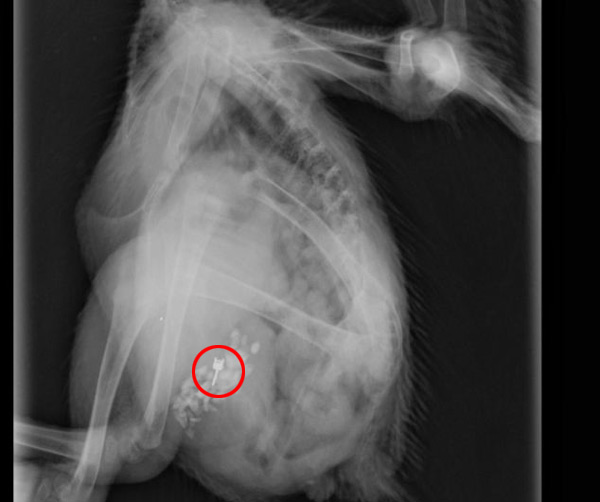

அதன்பின் மற்றுமொரு வைத்தியரை நாடியுள்ளார் கிளெயர். அங்கு எக்ஸ்ரே எடுக்கப்பட்டுள்ளது. இதில் குடல்பையில் சிக்கியிருப்பது உறுதியாகியுள்ளது. எனவே மலம் மூலம் வெளியேற்ற முயற்சிகள் மேற்கொள்ளப்பட்டது. அது கைகூடவில்லை.

இதனையடுத்து மிருக வைத்தியரைத் தொடர்புகொண்ட போது ‘இது வயிற்றின் உட்பகுதியில் காதணி சிக்கியுள்ளது. இது வெளியில் வராது. எனவே அறுவை சிகிச்சை மூலமே காதணியை மீட்க முடியும்’ என வைத்தியர் தெரிவித்துள்ளார்.